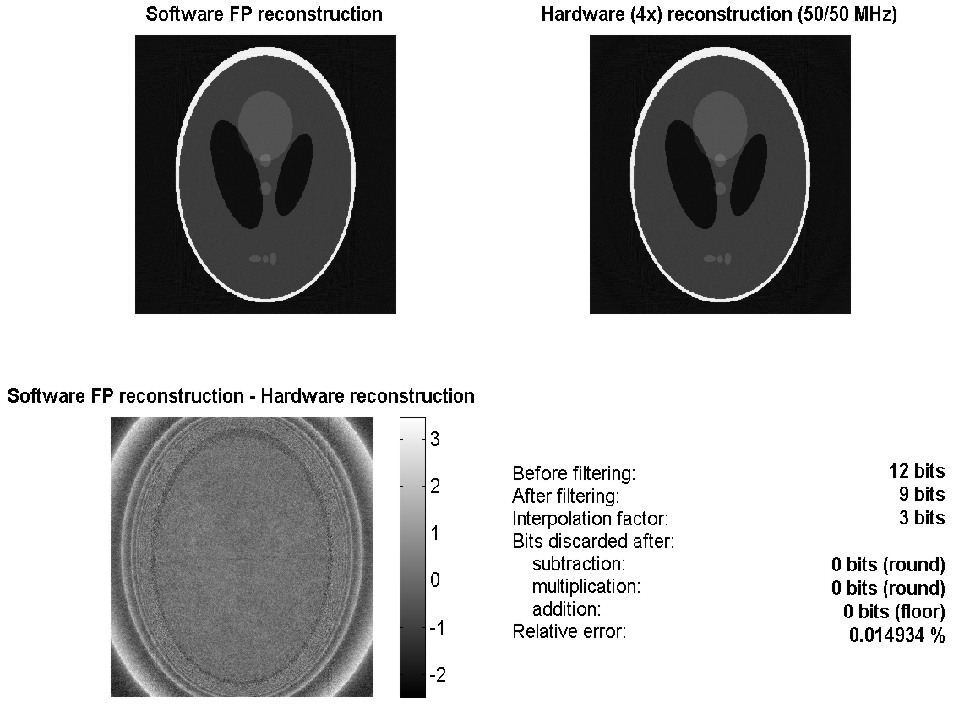

Backprojection result: Software floating point vs. Hardware fixed point